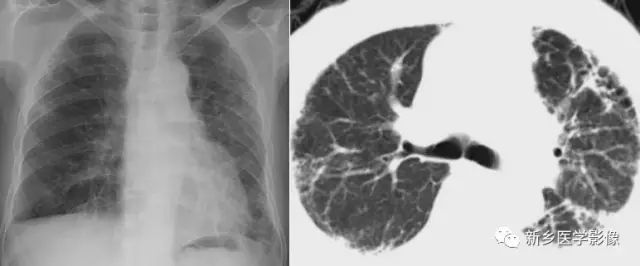

肺结核空洞CT图

a. 肺窗;b.纵隔窗,显示右上肺薄壁空洞(↑)

肺癌空洞CT图

a. 肺窗;b.纵隔窗,显示左上肺厚壁空洞(↑),内壁不规则,见壁结节